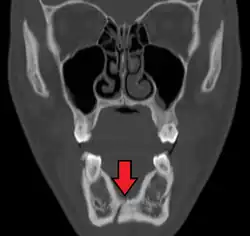

Computed tomography

Computed tomography is the most sensitive and specific of the imaging techniques. The facial bones can be visualized as slices through the skeletal in either the axial, coronal or sagittal planes. Images can be reconstructed into a 3-dimensional view, to give a better sense of the displacement of various fragments. 3D reconstruction, however, can mask smaller fractures owing to volume averaging, scatter artifact and surrounding structures simply blocking the view of underlying areas.

Towne's view of a bilateral condyle fracture. White arrow is a fracture on the neck of the condyle. Black arrow shows the condyle pulled to the medial. The same injury can be seen on the opposite side -

3D CT reconstruction of mandible fracture, white arrow marks fracture, red arrow marks moderate displacement and open bite -